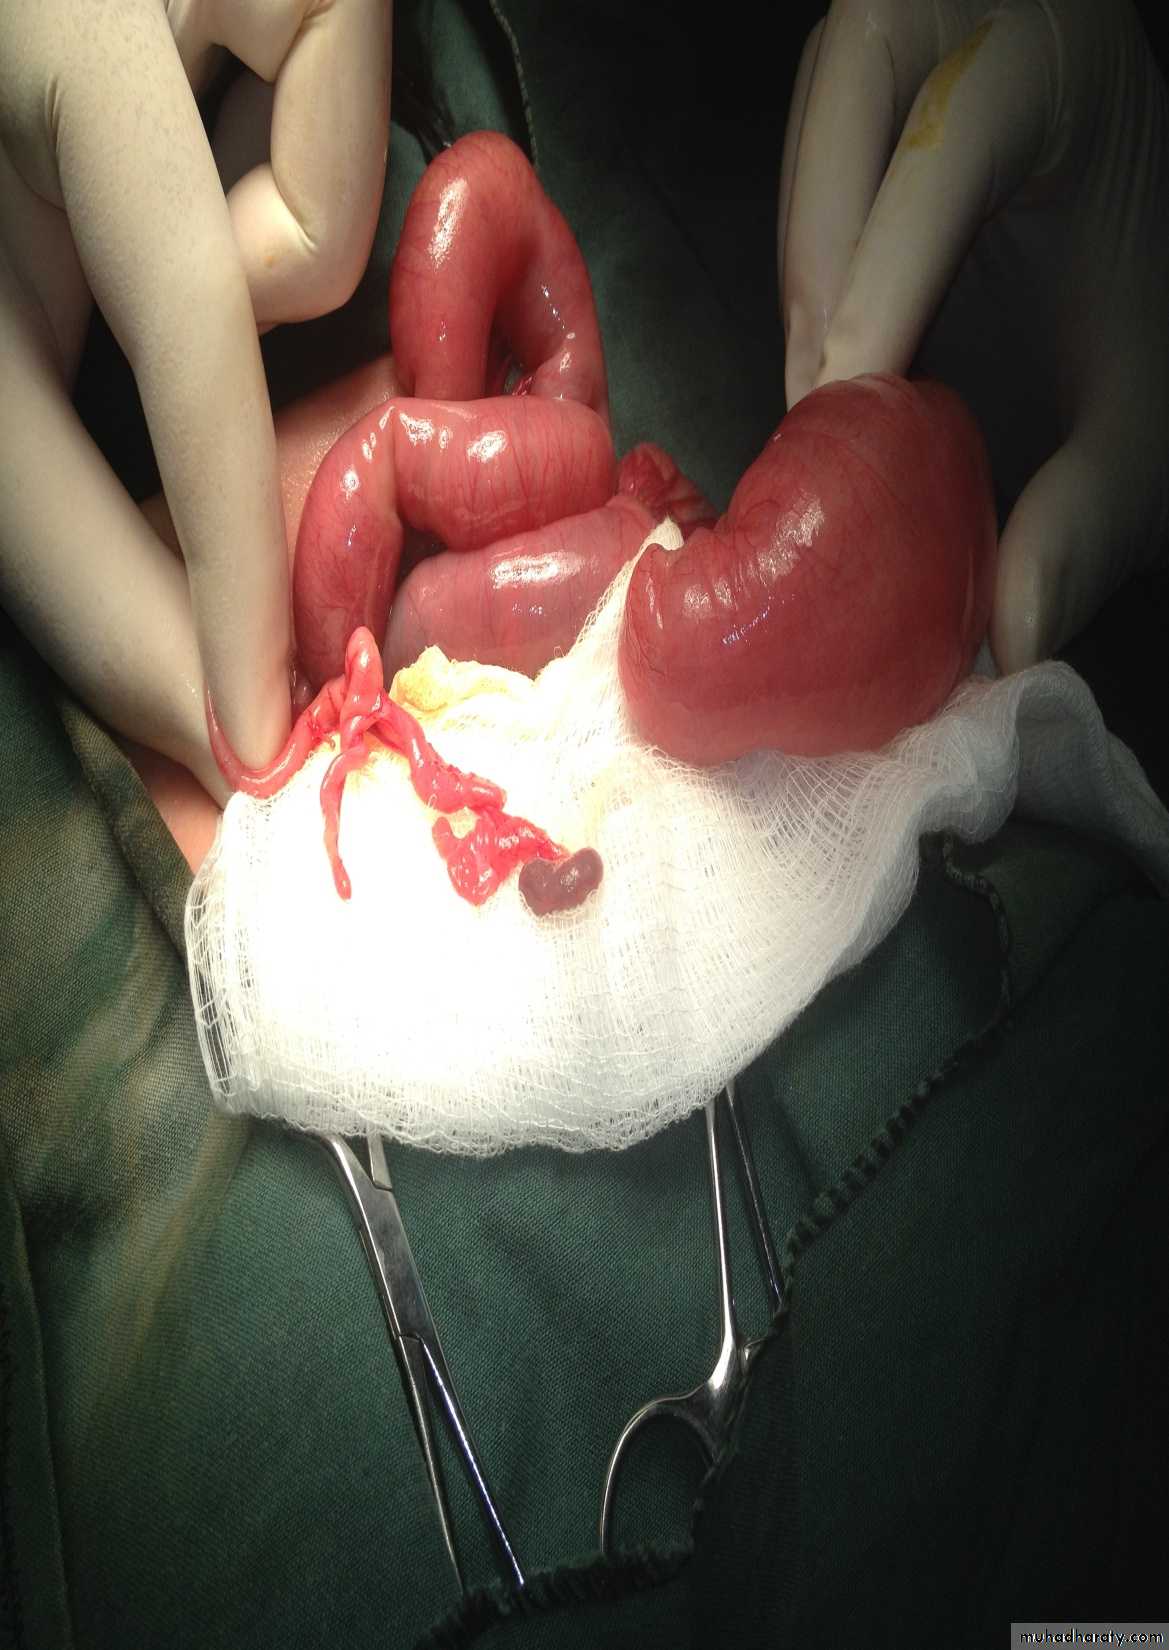

Intussusception

First photo:

Presentation:• Pull leg to abdomen

• Severe screaming

• Red current jelly stool

Third photo:

• Sausage massIn this video we see that the surgeon pull not push the intestine